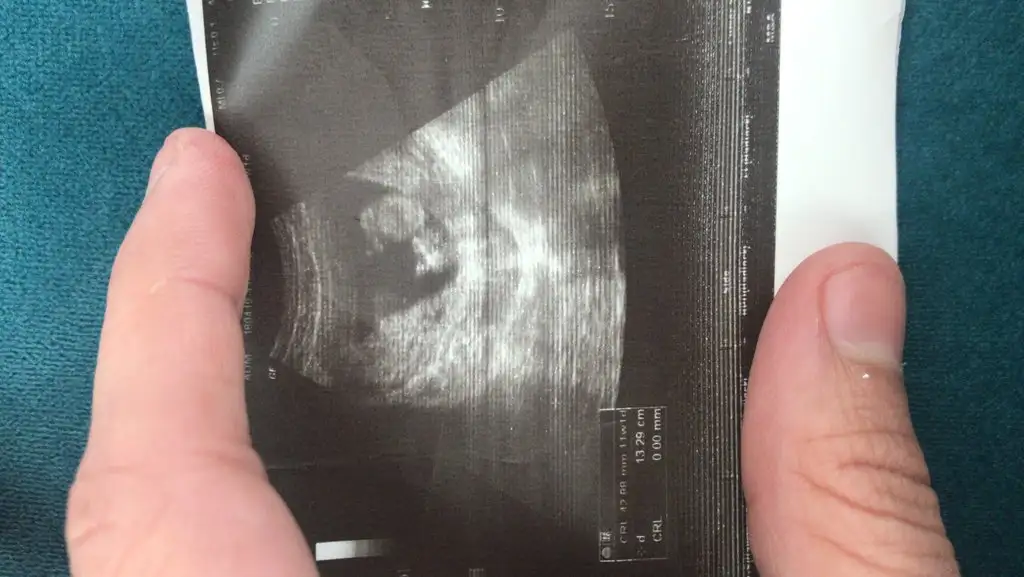

Hayırlısı olsun cinsiyeti öğrendinmi bide sağ mı sol taraftarı acaba13 haftalık. Cinsiyet tahmini olan var mı :)